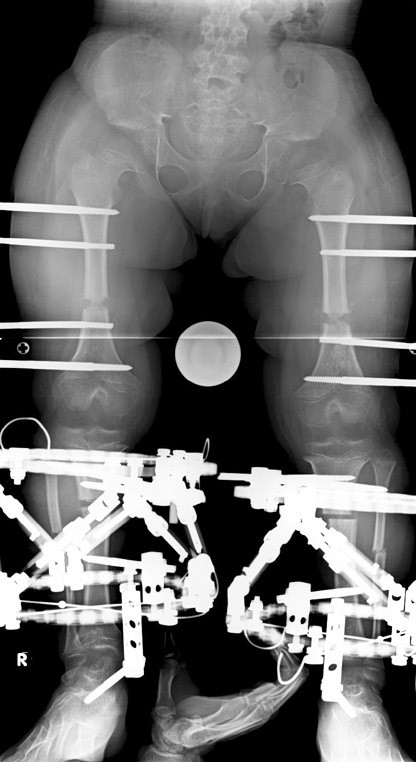

Cücelerde boy kısalığı için uyguladığımız boy uzatma programında sadece boy uzatmayı değil aynı zamanda ayak bileği, diz , kalça ve el bileği deformitelerinin düzeltilmesini ve lomber hiperlordozun azaltılmasını amaçlamaktayız. Lomber hiperlordozun azaltılması yetişkin yaşlarda spinal stenoz riskini azaltır. Başvuru anındaki yaşına göre iki tip tedavi stratejisi bulunmaktadır.

6-8 yaşları arasında Femur (uyluk) ve tibiada (bacak) toplam 10cm boy uzatma (6cm femur ve 4 cm tibia) Parantez bacak deformitesinin düzeltilmesi Ortalama eksternal fiksasyon tedavi süresi = 5 ay İkinci, üçüncü ve dördüncü boy uzatmalar Yetişkin stratejisinde (aşağıda) olduğu gibi Alt uzuvlarda (Diz üstü ve altı dahil) toplam 30-35 cm boy uzatma Üst uzuvlarda toplam 10-12 cm boy uzatma

12-14 yaşları arasında Her iki tibiada toplam 10-15cm boy uzatma (iki seviyeli uzatma) Proksimal tibianın varus deformitesini proksimal osteotomi ile düzeltilmesi Distal tibianın varus deformitesi distal osteotomi ile düzeltmesi Distal tibianın varus deformitesi distal osteotomi ile düzeltmesi Boy uzatmanın sonunda lateral kollateral ligamentin gerilmesi Ortalama eksternal fiksasyon tedavi süresi = 8-10 ay